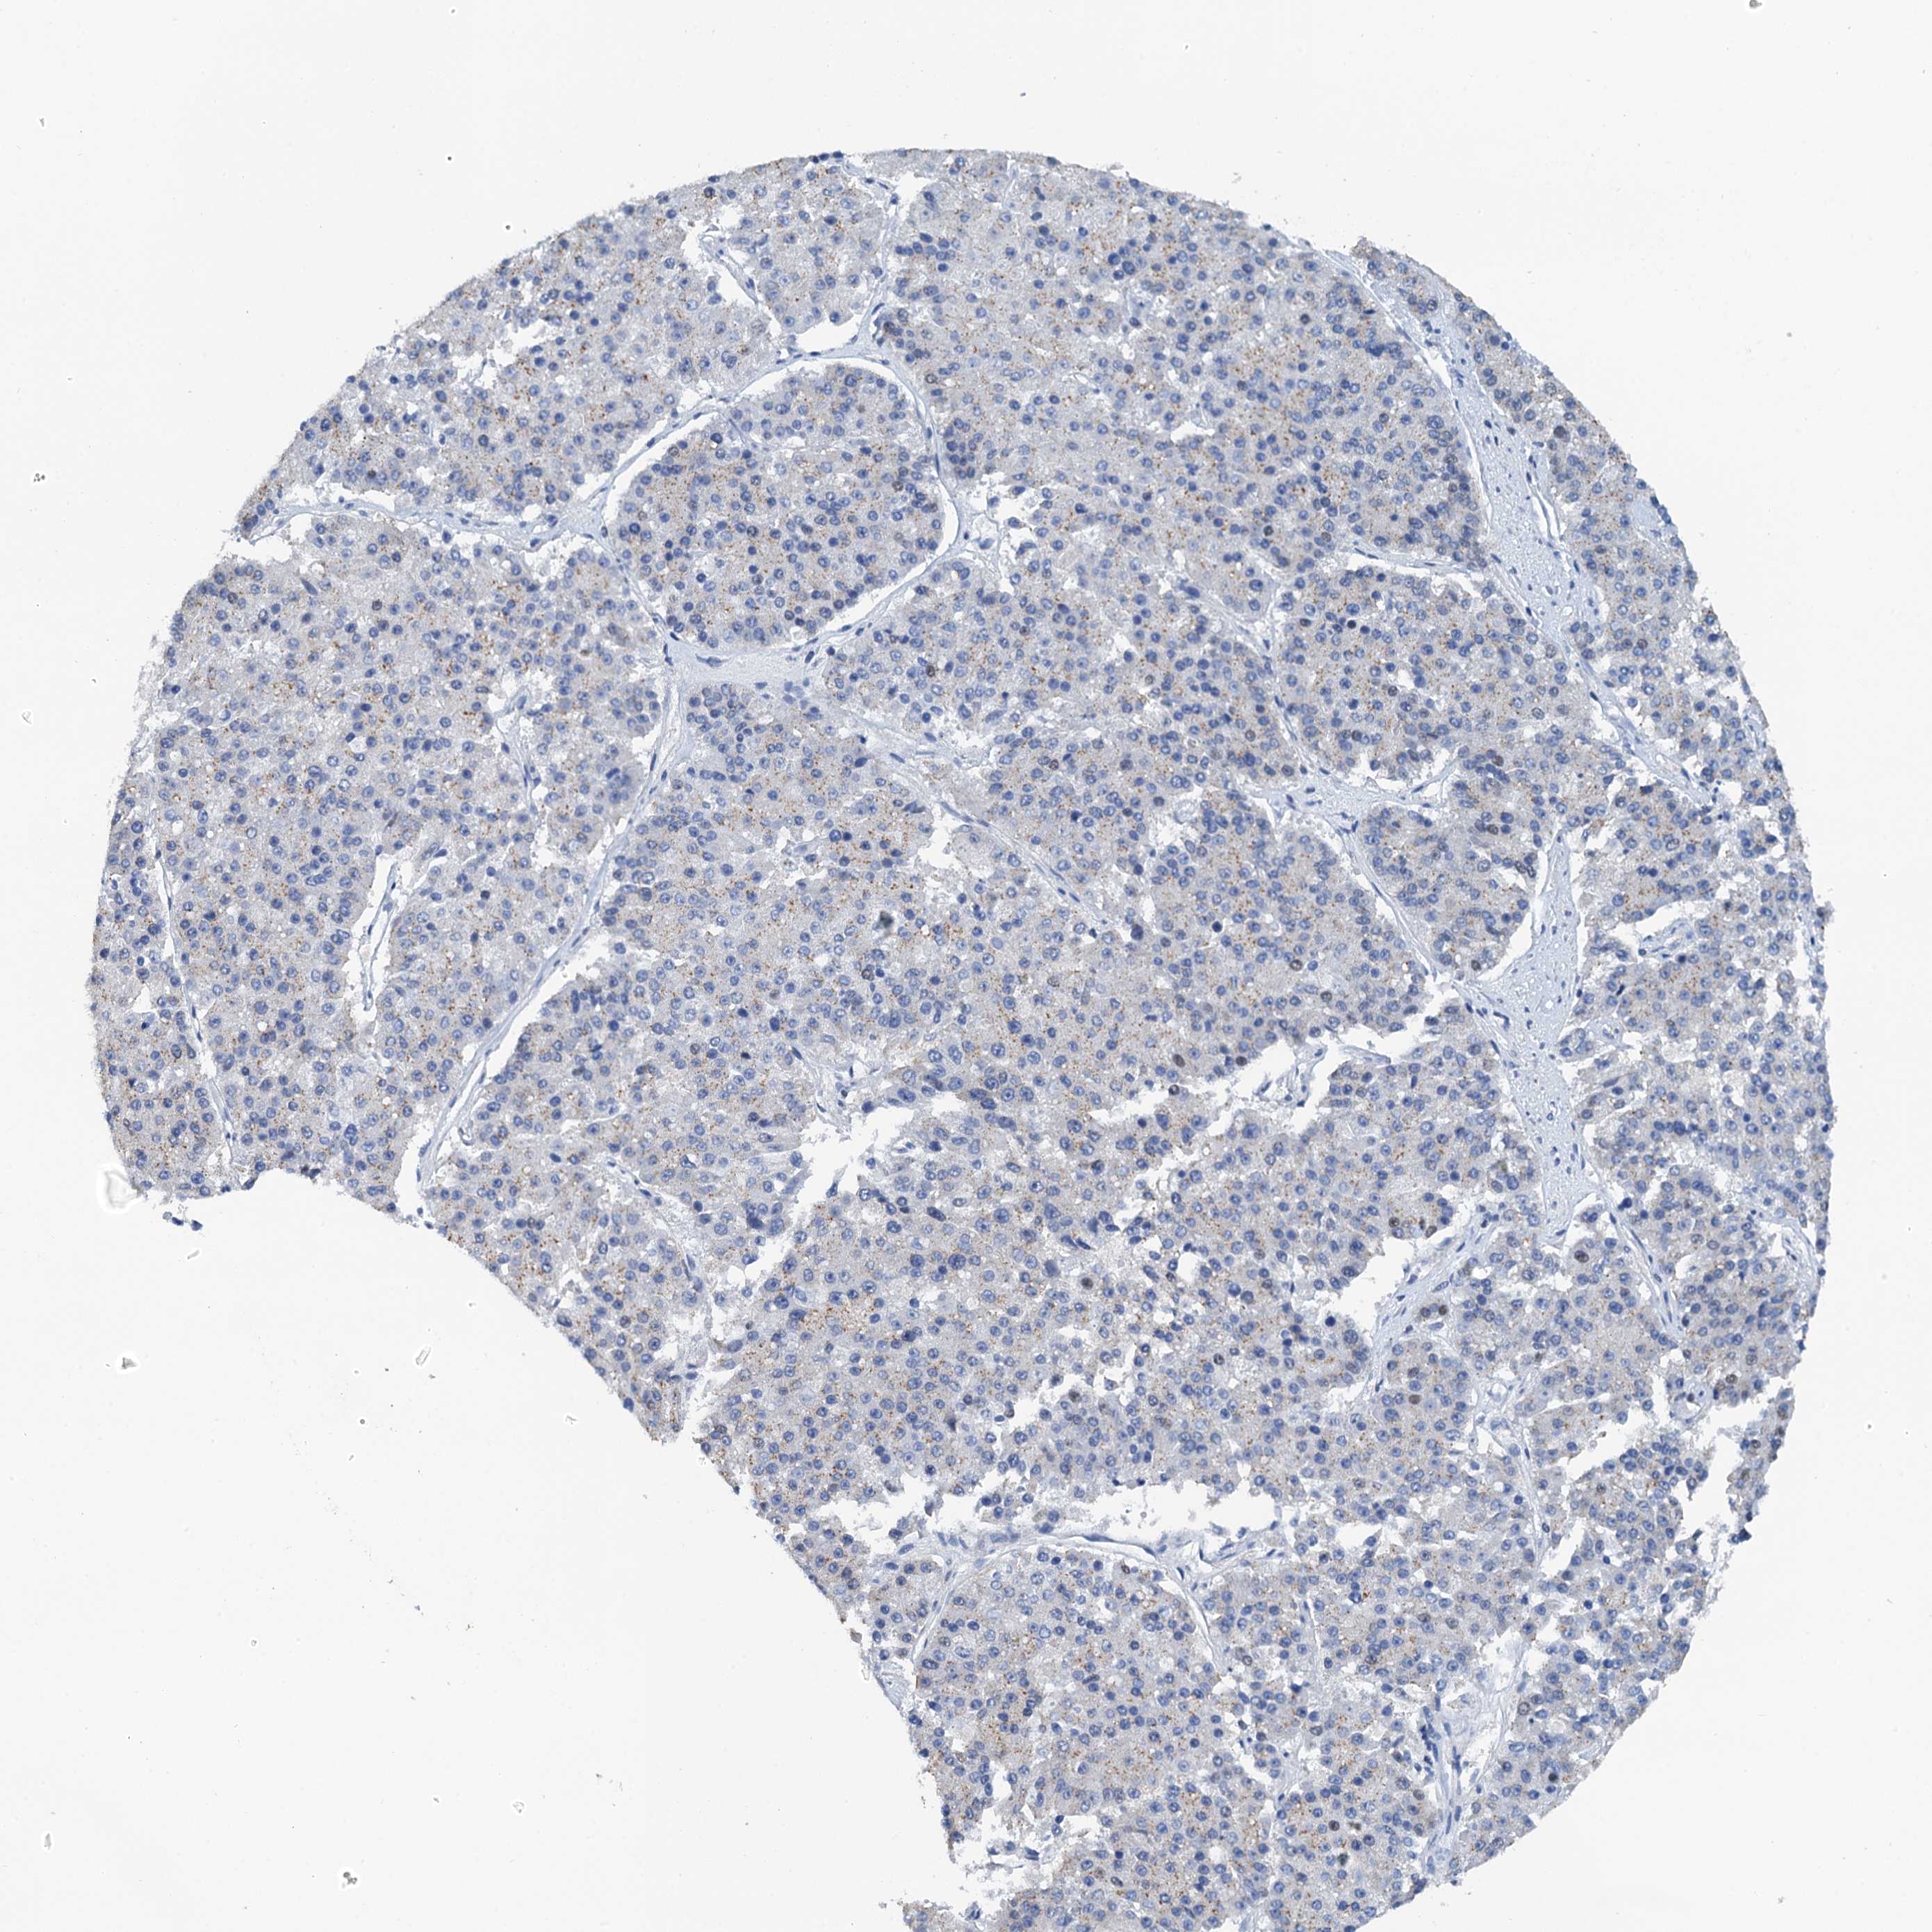

PANCREATIC CANCER - Protein expressioni

A mouse-over function shows sample information and annotation data. Click on an image to view it in a full screen mode. Samples can be filtered based on level of antibody staining by selecting one or several of the following categories: high, medium, low and not detected. The assay and annotation is described here.

Note that samples used for immunohistochemistry by the Human Protein Atlas do not correspond to samples in the TCGA dataset.

Antibody stainingi

Antibody staining in the annotated cell types in the current human tissue is reported as not detected, low, medium, or high, based on conventional immunohistochemistry profiling in selected tissues. This score is based on the combination of the staining intensity and fraction of stained cells.

Each image is clickable and will lead to virtual microscopy that enables deeper exploration of all samples and also displays staining intensity scores, fraction scores and subcellular localization as well as patient and tissue information for each sample.

Antibody HPA040256

Antibody HPA040381

Adenocarcinoma, NOS